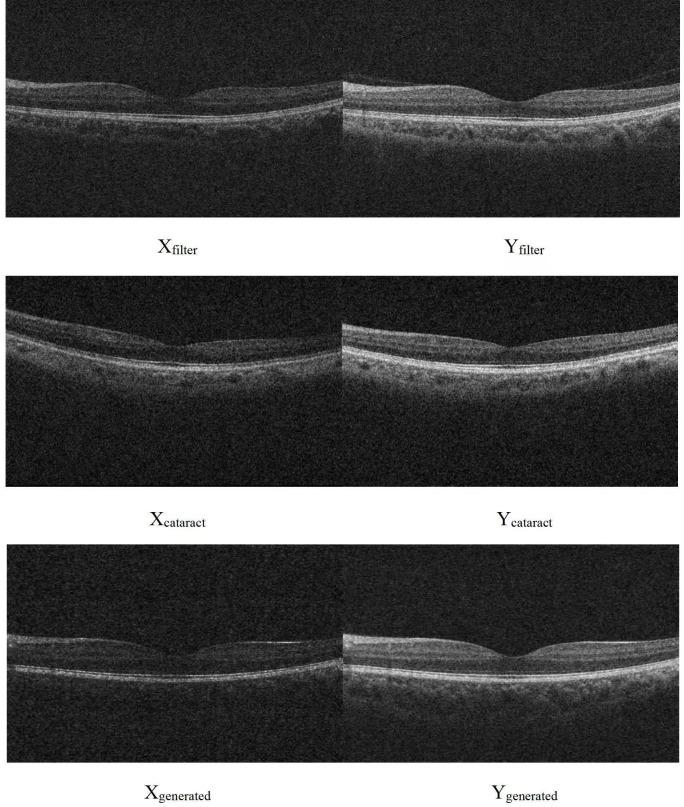

In this cross-sectional study, a spectral-domain OCT (Zeiss Cirrus 5000, Germany) was used to scan the macula of 510 eyes from 272 Chinese subjects. Optical media opacity was simulated with an algorithm for training set (420 normal eyes). Images for three test sets were from the following: 56 normal eyes before and after fitting neutral density filter (NDF), 34 eyes before and after cataract surgeries and 90 eyes processed by algorithm. GANs of pix2pix was trained with training set and restored blurred images in test sets. Structural similarity index (SSIM) and peak signal-to-noise ratio (PSNR) were used to evaluate the performance of GANs.

PSNR for test sets before and after image restoration was 18.37±0.44 and 19.94±0.29 for NDF (p<0.01), 16.65±0.99 and 16.91±0.26 for cataract (p=0.68) and 18.33±0.55 and 20.83±0.41 for algorithm regenerated graph (p<0.01), respectively. SSIM for test sets before and after image restoration was 0.85±0.02 and 1.00±0.00 for NDF (p<0.01), 0.92±0.07 and 0.97±0.02 for cataract (p<0.01) and 0.86±0.02 and 0.99±0.01 for algorithm regenerated graph (p<0.01), respectively.